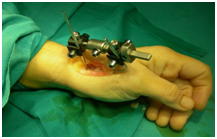

After an open debridement of the first carpometacarpal joint (Figure 2) we apply, under x-ray control, a mini ex-fix system3,5 (Figure 3).

Figure 2 After an open debridement of the first carpometacarpal joint.